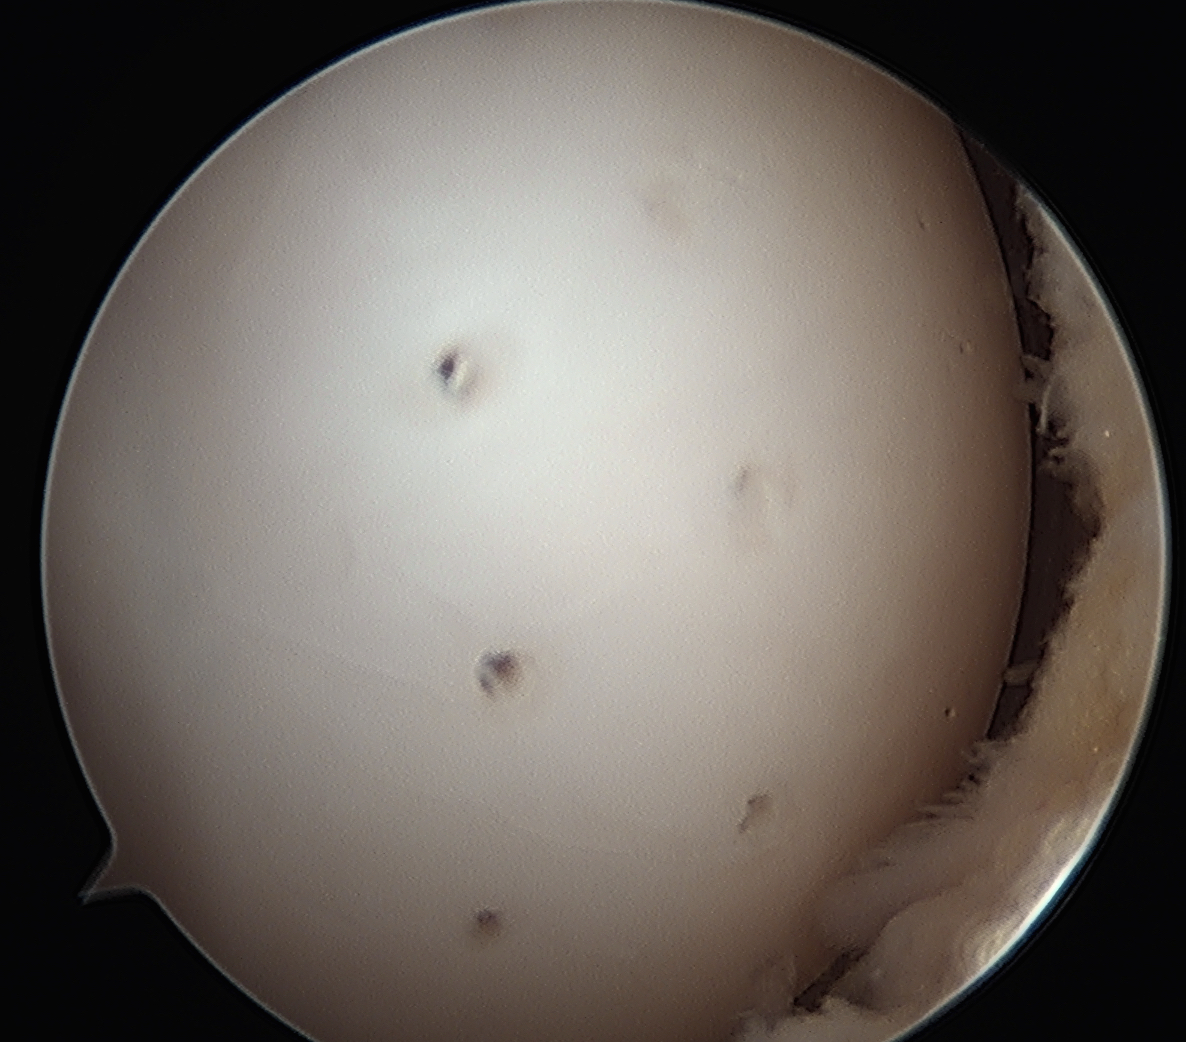

Cartilage intact on arthroscopy

In a stage 1 lesion there is no cartilage breach

- the MFC / LFC looks normal